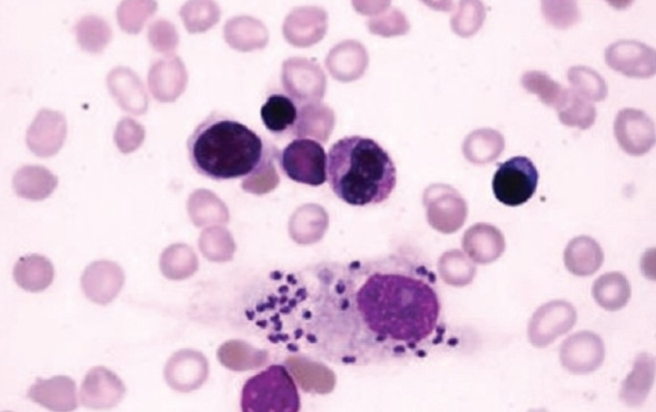

Leishmania spp.

Leishmania spp.